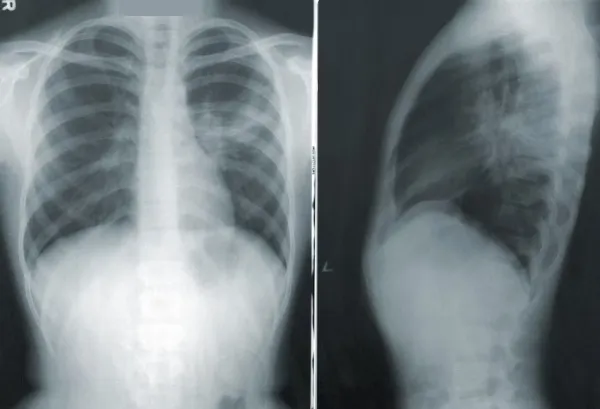

Врач также отметил, что чаще всего это заболевание выявляется на поздних сроках. Именно поэтому рекомендовано раз в год делать флюорографию или рентгенографию.

- Рентген более предпочтителен. КТ была бы еще лучше, но это дорогостоящий метод исследования. При регулярном обследовании можно "поймать" рак на ранней стадии, а чем менее распространенный процесс, тем больше у нас шансов помочь больному.